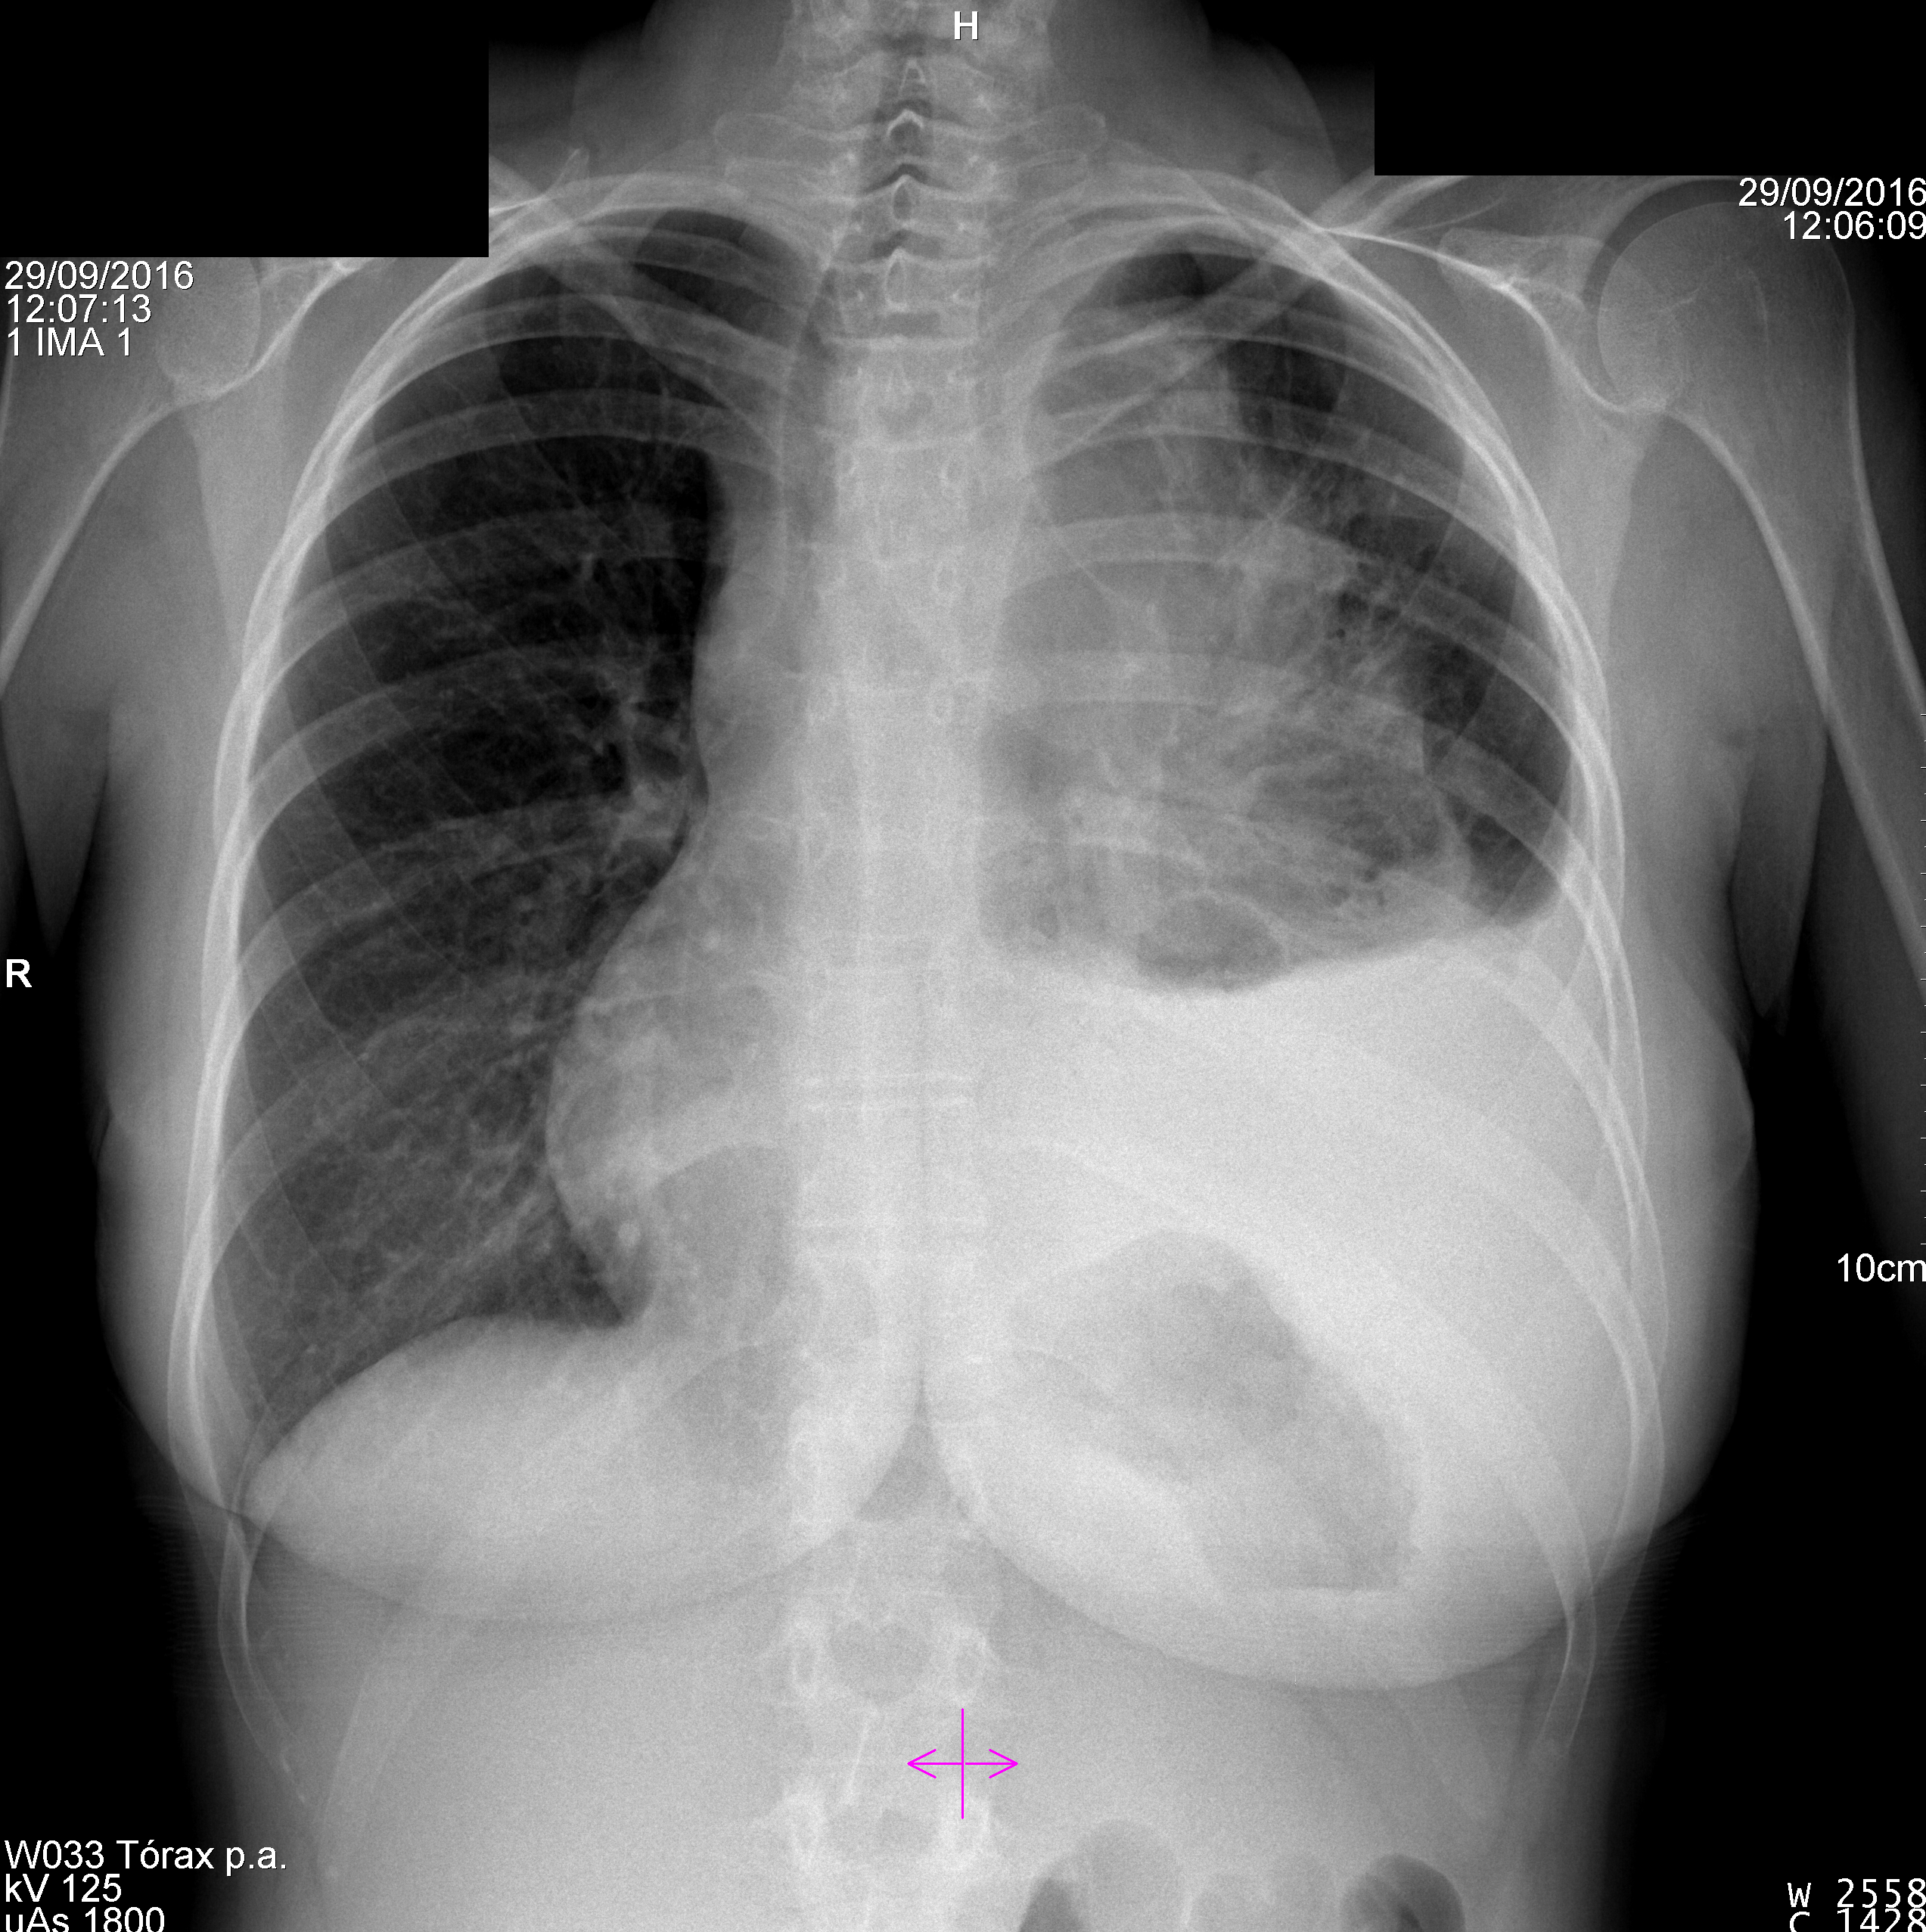

La siguiente prueba a realizar, el día 29 de septiembre de 2016, es una radiografía simple de tórax para evaluar otras posibles patologías, puesto que presenta menor radiación que un TAC. A continuación se establece el diagnóstico, tratamiento y se le cita de nuevo en abril de 2017, ya no estará embarazada, se le realiza una radiografía simple de tórax, para evaluar la respuesta al tratamiento (cirugía, radioterapia y quimiterapia).